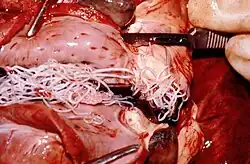

- Heartworm is a dog parasitoid. It is hard to eliminate and can be fatal; prevention, however, is easily achieved using medication. As the name suggests, an infected mosquito injects a larva into the dog's skin, where it migrates to the circulatory system and takes up residence in the pulmonary arteries and heart, growing and reproducing to an alarming degree. The effects on the dog are quite predictable: cardiac failure leading to death. Treatment of an infected dog is difficult, involving an attempt to poison the healthy worm with arsenic compounds without killing the weakened dog, and may not succeed. Prevention is recommended via the use of heartworm prophylactics, which contain a compound that kills the larvae immediately upon infection without harming the dog. Often they are combined with other parasite preventives.